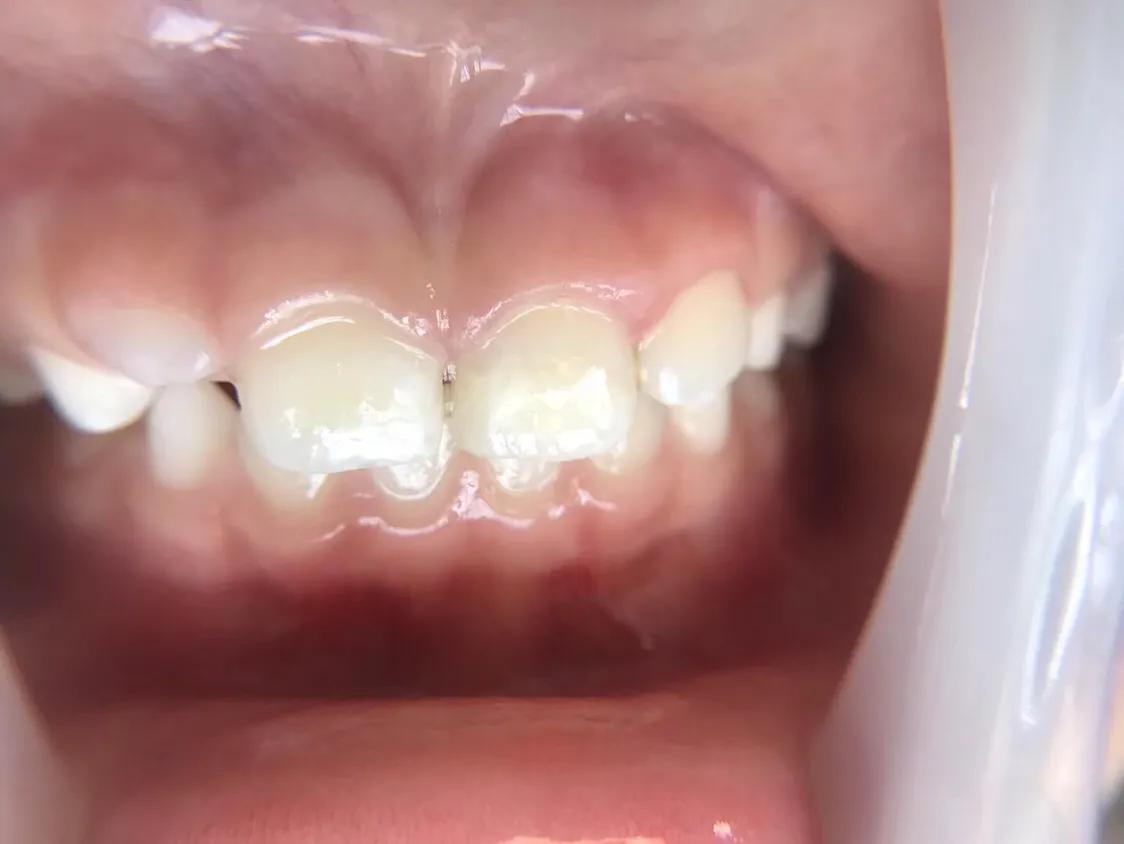

1.龋齿俗称蛀牙

龋齿是因为口腔里的细菌利用糖分繁殖分解产酸引起牙体组织的变性,结构破坏,形成蛀洞。牙齿会出现酸甜食物痛,冷热刺激痛,食物嵌塞入洞痛。

龋齿的处理方法 补牙

未按规定处理将面临的处罚 随着龋洞不断的加深,将会出现牙神经痛,牙根发炎,让你寝食难安,长期拖延不处理有拔除患牙的可能。